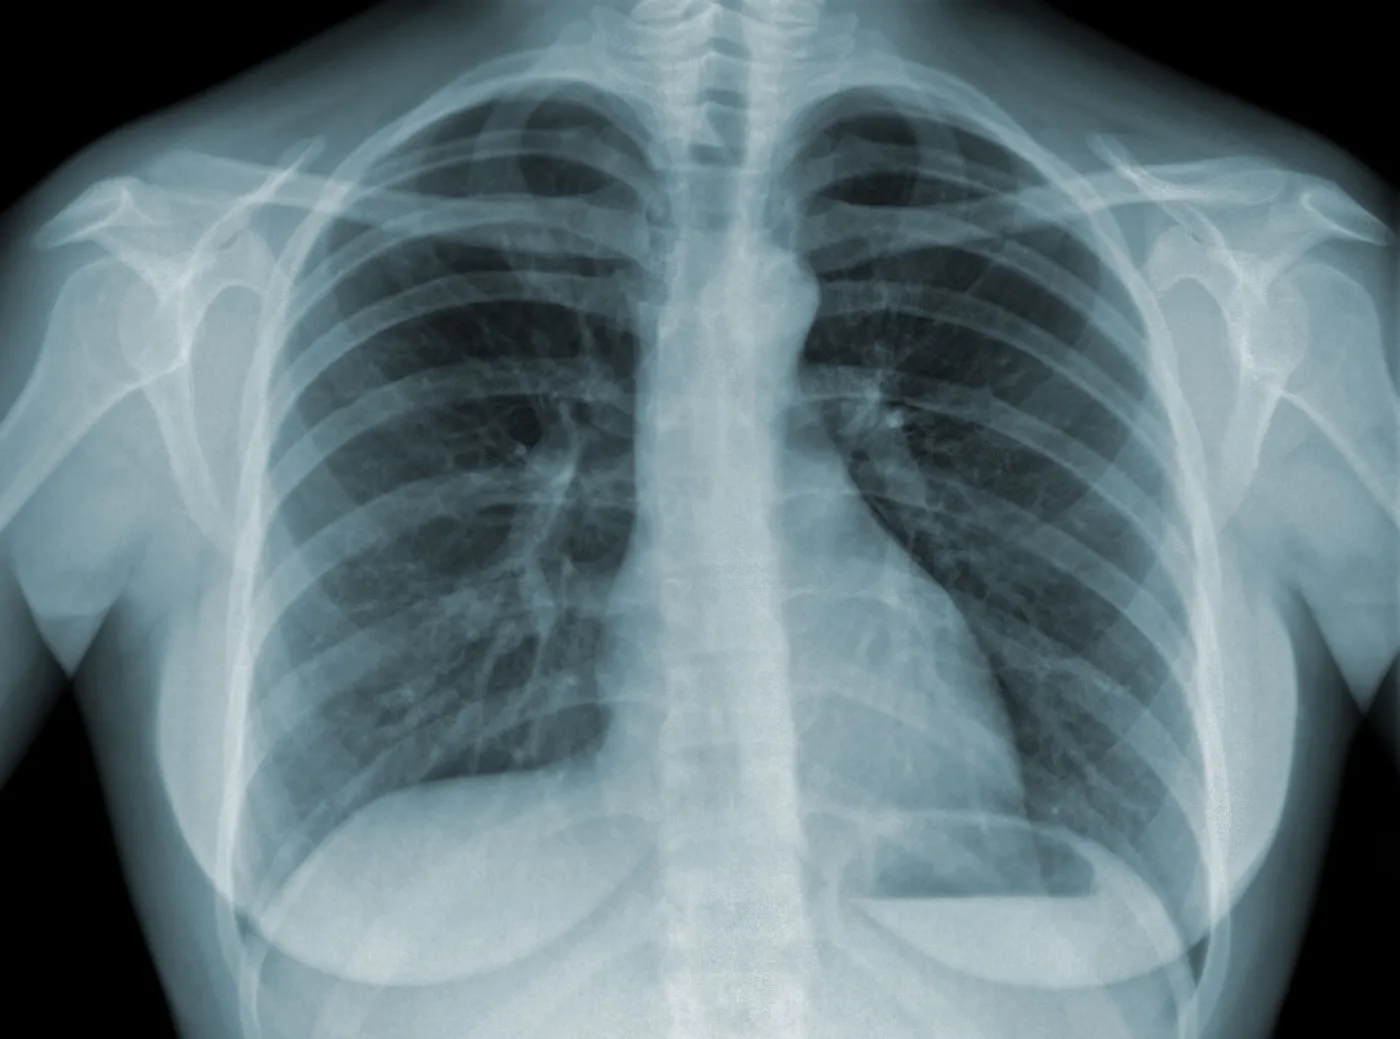

RTG płuc gruźlica

<p>RTG płuc</p>/Shutterstock

Hiszpańscy naukowcy opracowali system szybkiej identyfikacji COVID-19 w organizmie pacjenta na podstawie zdjęć rentgenowskich. Bazuje on na wykorzystaniu sztucznej inteligencji.

Hiszpański badacz wyjaśnił, że dzięki programowi bazującemu na sztucznej inteligencji zdjęcie rentgenowskie płuc poddawane jest szybkiej analizie, podczas której porównywane są inne rentgenogramy wykonane u chorych na COVID-19 pacjentów.